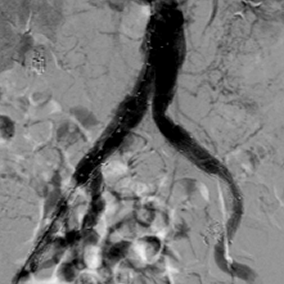

术中行右侧髂内动脉IBD及腹主动脉-双侧髂动脉瘤支架隔绝

术后半年复查CT显示腹主动脉-双侧髂动脉瘤完全隔绝,右侧髂内动脉血流通畅。